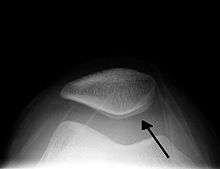

| A traumatic right knee effusion. Note the swelling lateral to the kneecap as marked by the arrow. | |